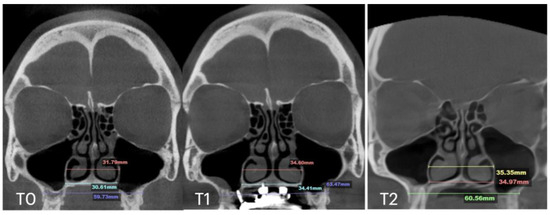

| T0 | T1 | T2 | T0 | T1 | T2 | T0 | T1 | T2 | T0 | T1 | T2 | T1 | |

| Case A | 30.84 | 38.15 | 38.37 | 59.22 | 66.37 | 67.11 | 32.8 | 39.33 | 39.48 | 28.01 | 32.88 | 33.38 | 10.5 |

| Case B | 30.61 | 34.41 | 34.97 | 59.73 | 63.47 | 60.56 | 31.79 | 34.6 | 35.35 | 29.18 | 31.38 | 34.59 | 5.7 |

| Case C | 28.40 | 38.32 | 36.72 | 53.63 | 62.43 | 59.80 | 31.29 | 38.45 | 38.51 | 29.15 | 35.8 | 35.36 | 8.47 |

| Case D | 26.25 | 33.27 | 31.54 | 55.9 | 61.84 | 60.37 | 33.98 | 35.94 | 38.09 | 29.77 | 29.24 | 29.02 | 6.2 |